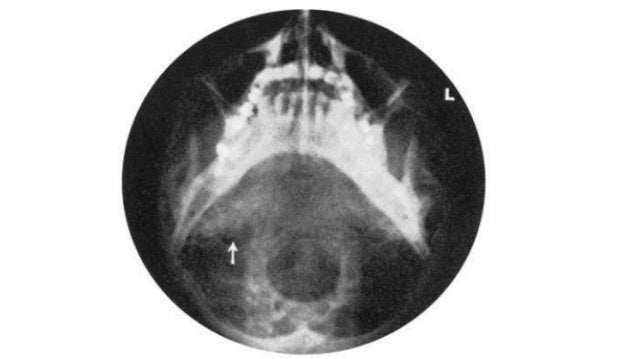

Bilateral Clinical Pathology Of The Temporal Bone ~ Fulltext

Bilateral Clinical Pathology of the Temporal Bone ~ Fulltext benthamopen.com

fig benthamopen